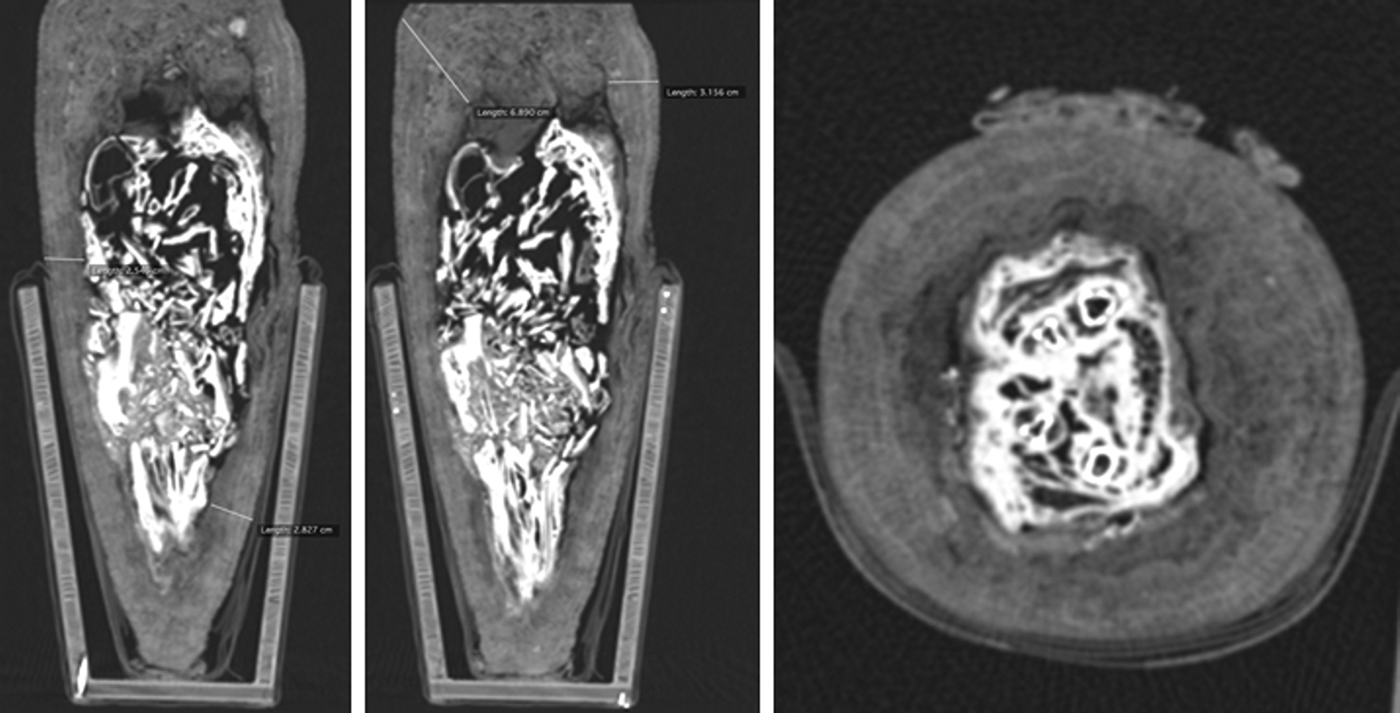

The remaining mummies were conical-shaped bundles. Imaging demonstrated the presence of non-skeletal and skeletal remains: two bundles contained a core of feathers and eggshell, supported by linen rolls (Figure S2). Eight bundles contained avian skeletal material, all of which appeared consistent in size and morphology with ibis species. Two bundles contained incomplete skeletal remains of a single ibis individual, which appear to be completely skeletonised, indicating that soft tissue or feathers were not present at the time of wrapping (Figure S3). Four bundles contained unidentifiable avian skeletal remains that were mummified in toto, of which two were the incomplete skeletal remains of a single individual (Figure S4), and two were probably complete ibises at the time of mummification. The latter had suffered significant post-depositional damage to the thoracic spine (Figure 4). This suggests a lack of evisceration during mummification, which resulted in biological degradation of the internal organs, which in turn resulted in the collapse of delicate structural elements, such as the ribcage (Ikram Reference Ikram2015: 22).

Figure 4. Axial and reformatted coronal CT slices showing the contents of 11501 as an example of mummification in toto of a complete ibis (reproduced by permission of the Manchester Museum and the Central Manchester University Foundation Trust).

Clinical imaging and analysis of damaged areas allows for the delineation of stages in the construction of the mummy bundles (Table 3). This includes a distinct similarity in the radiodense appearance of the bundle cores due to the application of a resinous substance during their preparation. Experimental work has shown this is to be a vital step, both for preservation and for practical reasons by acting as an adhesive to fix the linen layers (Atherton & McKnight Reference Atherton and McKnight2014). It is evident that stage 1 is comparable to animal mummies excavated by the EES in the Falcon Catacombs, where animal remains were simply “sewn into a coarse linen bag” (Davies & Smith Reference Davies and Smith2005: 8) before being shaped into bird-like forms using linen pads and rolls (Figure S4). The major variation in this stage between the Falcon Catacombs and the South Shaft mummies, however, was the amount of linen used, which varied greatly in thickness between 5 and 50mm at the densest point (Figure 4).